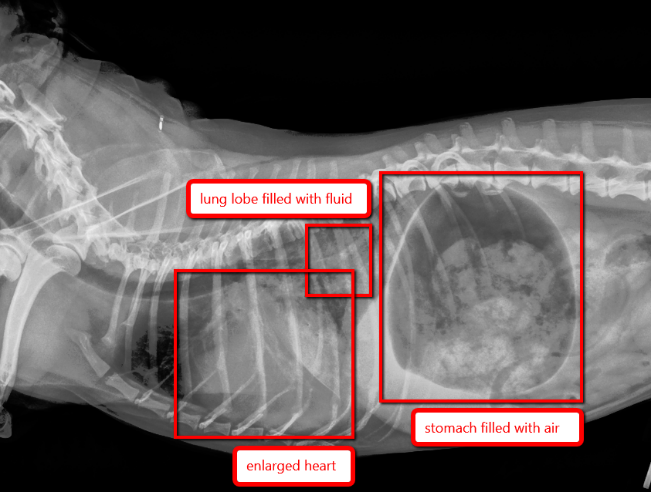

On the chest x-rays, Dr. Rose could see that Lucy’s heart was quite enlarged. Her larger-than-normal heart was caused by a poorly functioning valve. The valve was not closing properly due to chronic degenerative valvular disease, a common disorder in older dogs like Lucy. The degeneration and thickening in the valve was causing blood to regurgitate into her left atrium, leading to cardiac enlargement.

The most striking feature of the “Before” x-ray is the fluid (called “pulmonary edema”) that is visible in the caudal lung lobes. The caudal lung lobes are typically the ones most affected by congestive heart failure. Here, these lung lobes are filled with fluid, instead of air, causing Lucy to cough and have difficulty breathing. Fluid on chest x-rays will appear white, whereas air will appear black. These lung lobes are much too white, and no normal black air is seen. In contrast, there is a lot of air in the stomach, which is caused when a dog struggles to breathe and gulps in air.